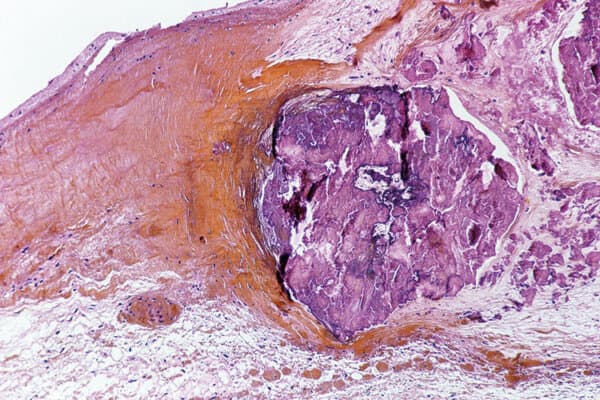

Science Photo Library/ Christol, D. / CNRI

Valve cardiaque attaquée par des streptocoques. Souvent, d’autres structures sont également touchées.